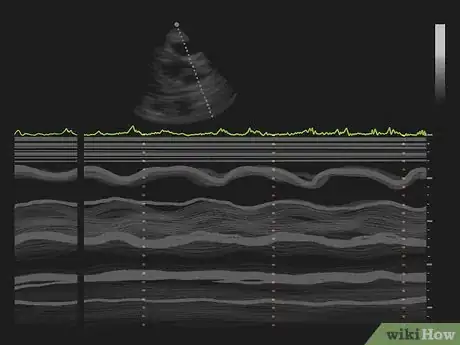

3Watch the monitor to determine what techniques the doctor uses. There are several different techniques the doctor may use. They enable the doctor to make different measurements.[10]

- M-Mode. This technique generates a outlines showing the heart's size, the chambers, and the thickness of the walls of the heart.